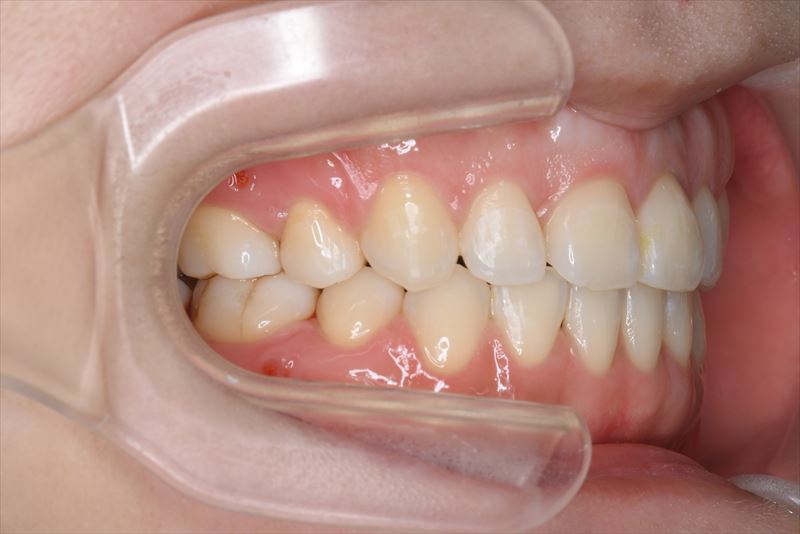

治療後

症状

叢生、口唇の突出

臼歯のみの咬合、口唇の閉鎖が難しい状況でした。抜歯を行い前歯を牽引することで、良好な側貌と緊密な咬合を獲得できました。